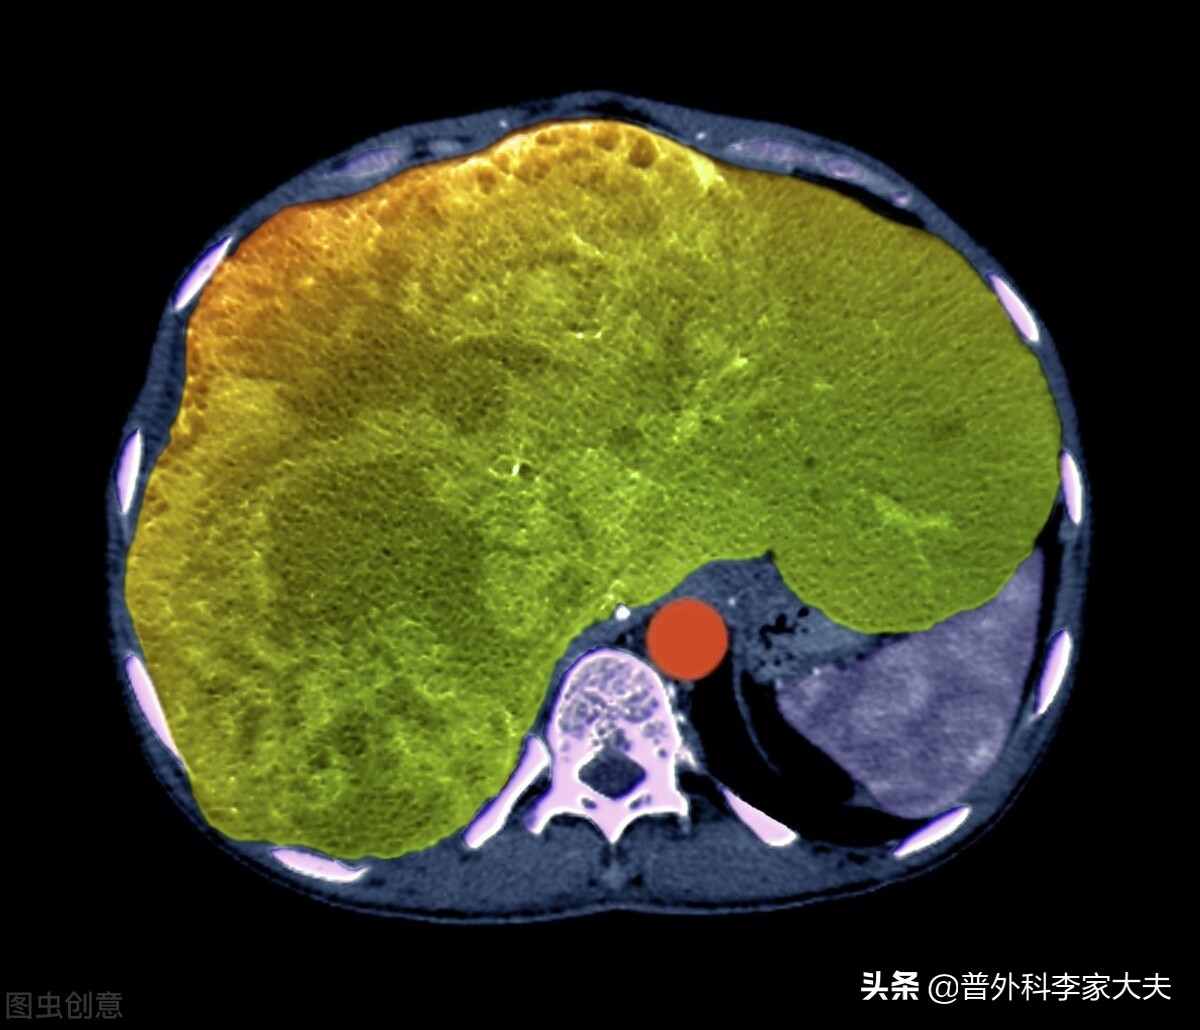

肝癌

从保护肝脏功能的角度来考虑:

肝脏承担着人体的胆汁分泌、代谢功能、解毒与吞噬或免疫作用等,对于肝癌晚期患者来说,患者的肝脏储备功能有限,甚至因为肝癌疾病原因,会导致患者肝功能不好。因此,避免高脂饮食,给患者带来的肝脏胆汁分泌负荷太重的问题,也要避免高蛋白饮食,给患者带来的血氨代谢障碍,而增加肝性脑病发生。同时,还要避免高糖饮食或不均衡饮食,给患者肝脏带来的糖代谢异常与其他物质代谢负担过重问题。另外,尽可能排除有毒外来物或进入人体会产生毒素的食物进食, 以减少它们给肝脏带来的解毒负担。宜少吃多餐、注意均衡营养饮食,提供患者肝脏能够承担的饮食代谢负荷,来进行营养物质的进食。